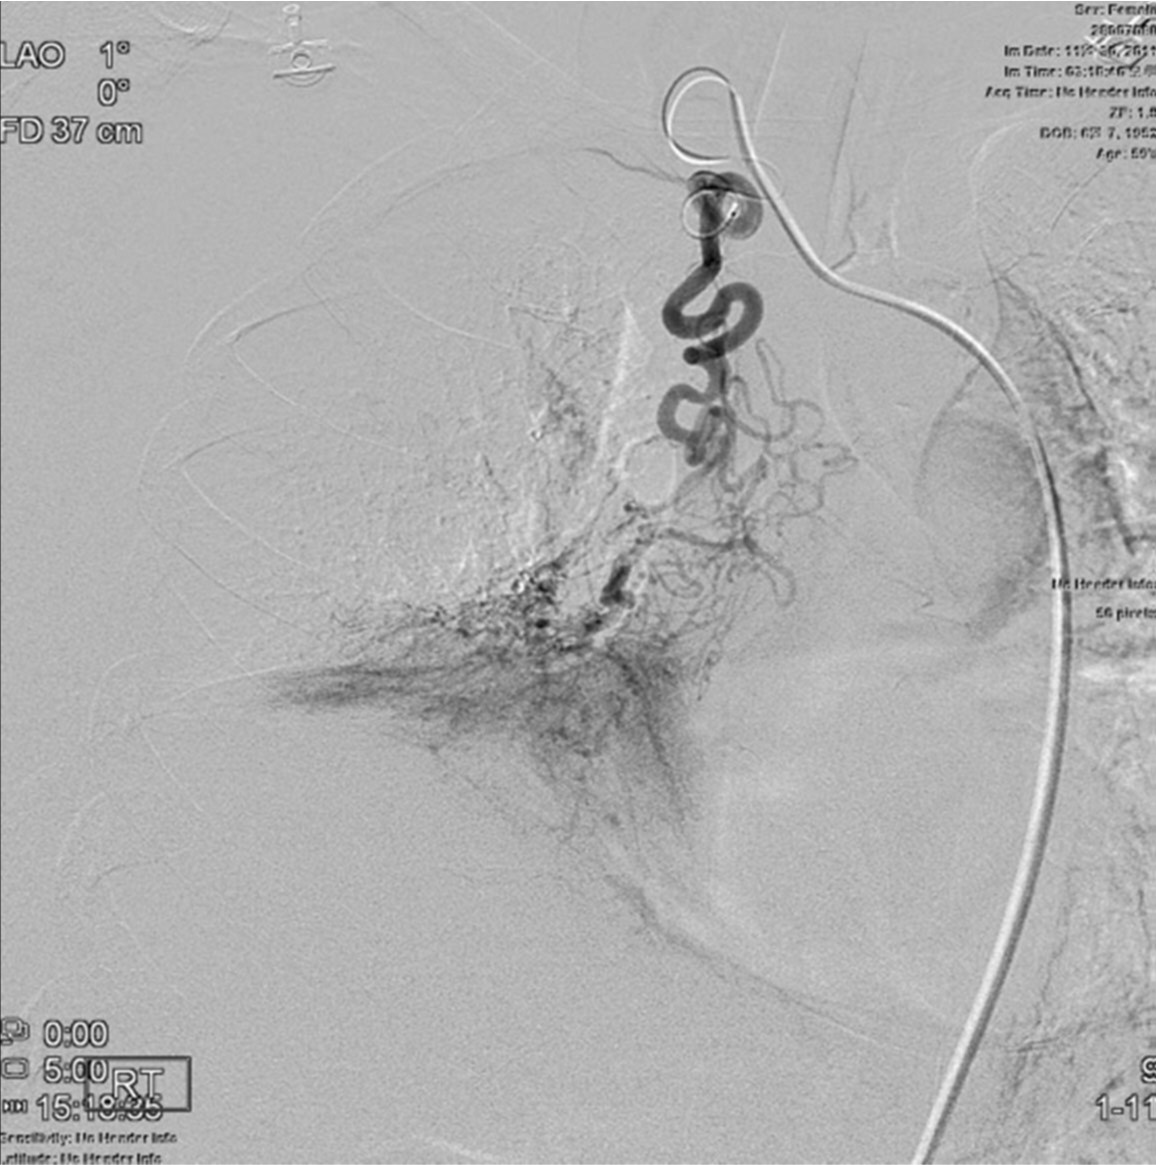

Fig. 3. A

Fig. 3A. Right subclavian arteriogram reveals hypertrophy of the right bronchial artery (arrow), originated from the proximal part of the right subclavian artery.

Fig. 3. B

Fig. 3B. Hypervascular parenchymal staining in the right lower lung field is demonstrated on selective angiogram of the right bronchial artery.